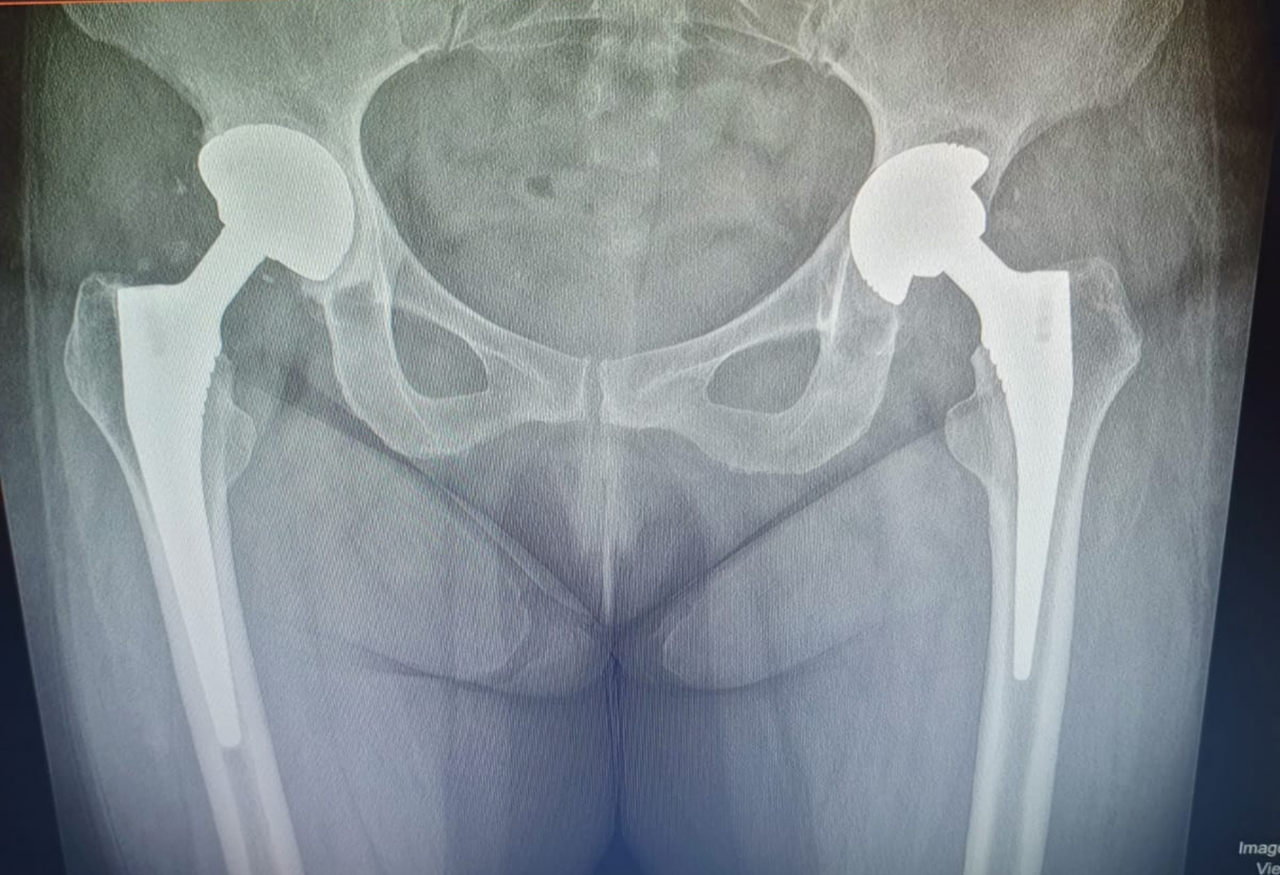

Prótesis de Cadera.

Procedimiento quirúrgico que reemplaza la articulación dañada de la cadera por una prótesis artificial, permitiendo recuperar la movilidad, reducir el dolor y mejorar la calidad de vida del paciente.